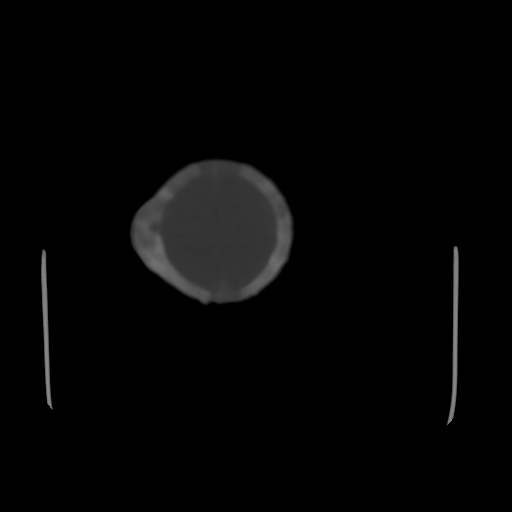

男,12天,自然分娩,其母发现右顶部头皮包块逐渐增大。

右顶部头皮血肿

右顶部头颅血肿(骨膜下血肿)

右顶骨呈膨胀性改变,骨纤维结构不良?

右顶部头皮血肿,可能是产道挤压所致。以后会慢慢恢复。

鉴别:骨膜下血肿,一般为产伤,应用产钳之类的吧

疑问:患儿脑白质密度比较低,基底节区密度比较高,类似于“双圈征”脑沟密度也偏高。该婴儿可有别的异常吗?反射正常吗?评分能达到5分吗?如果正常,就随诊观察吧。不正常要考虑到缺血缺氧性脑病。